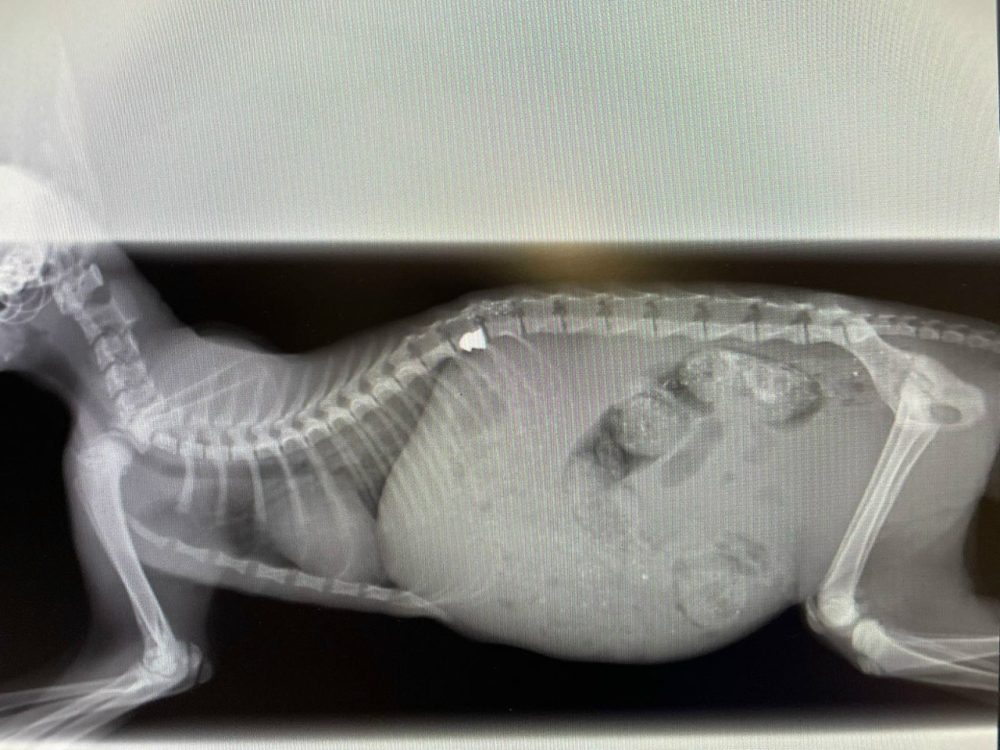

рэнтген коткі

Рэнтген кацяняці. Фота валанцёркі

Таццяна патэлефанавала валанцёрцы Маргарыце, якая адразу пагадзілася забраць кацяня. На наступны дзень тая адвезла яго ў мінскую клініку «Доктар Вет», дзе зрабілі МРТ і аперацыю па выманні кулі. Аднак у выніку стрэлу быў пашкоджаны пазваночнік, і заднія лапкі ў малога паралізаваныя.